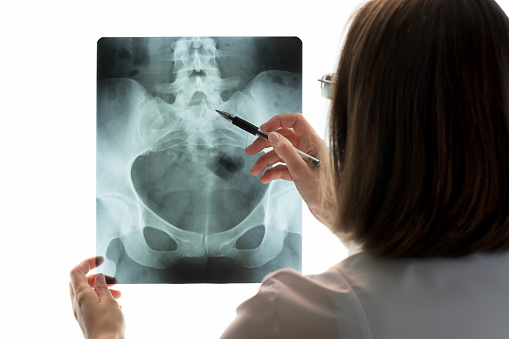

고관절 골절은 보통 엑스레이에 선명하게 나타나서 진단을 확인할 수 있습니다.

하지만 때로는 골절이 있어도, 골절이 작고 골절된 조각이 제자리에 있는 경우 정상으로 보이기도 합니다. 그래서 환자가 통증 등 증상을 계속 느끼고 설 수 없다면 작고 미세한 골절을 확인하기 위해서MRI(자기 공명영상)을 이용하기도 합니다.

CT(컴퓨터 단층 촬영)을 하기도 하지만 작은 고관절 골절을 발견하는 데에는 MRI보다 덜 정확합니다.